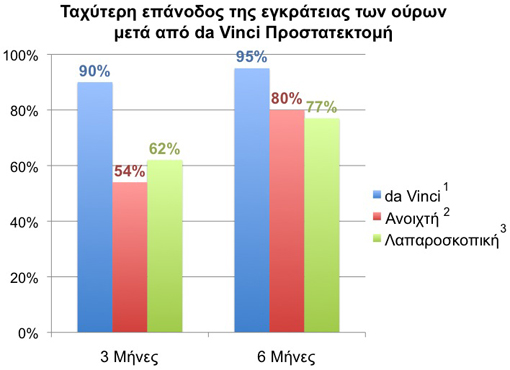

Οι ασθενείς με καρκίνο του προστάτη ανησυχούν επίσης για την εγκράτεια των ούρων και την σεξουαλική λειτουργία μετά την θεραπεία. Όλες οι μέχρι τώρα μεγάλες μελέτες δείχνουν ότι η da Vinci προστατεκτομή παρουσιάζει γρηγορότερη επάνοδο της εγκράτειας των ούρων και χαμηλότερα ποσοστά πόνου σε σύγκριση με τους ασθενείς που υποβλήθηκαν σε ακτινοθεραπεία (βραχυθεραπεία). Διάφορες επίσης μελέτες δείχνουν ότι οι ασθενείς που ήταν προηγουμένως σεξουαλικά ικανοί παρουσιάζουν πλήρη ανάρρωση της σεξουαλικής τους λειτουργίας (οριζόμενη σαν στύση ικανή για κολπική διείσδυση) μέσα σ’ ένα έτος από την da Vinci προστατεκτομη. Η περίοδος ανάρρωσης μπορεί να επιταχυνθεί μέσω ενός ειδικού προγράμματος ανάρρωσης της στυτικής λειτουργίας με την χρήση ασκήσεων και φαρμάκων.

- Ακράτεια ούρων: Εκτός των άλλων το σπουδαιότερο πλεονέκτημα της ρομποτικής προστατεκτομής είναι τα αυξημένα ποσοστά πρώιμης εγκράτειας των ούρων. Στα δικά μου χέρια οι μισοί και πλέον ασθενείς είναι εγκρατείς (χρησιμοποιώντας 0 με 1 πάνα ακράτειας) με την αφαίρεση του καθετήρα μία εβδομάδα μετά την ρομποτική προστατεκτομή. Αυτός είναι και ο λόγος που δεν εκτελώ πια την συμβατική λαπαροσκοπική ή και την ανοιχτή ριζική προστατεκτομή γιατί αυτές οι μορφές ριζικού χειρουργείου έχουν πολύ χειρότερα αποτελέσματα εγκράτειας σε σχέση με την ρομποτική επέμβαση. Οι υπόλοιποι ασθενείς υποφέρουν από προσωρινή και μικρού βαθμού ακράτεια, η οποία βελτιώνεται με την πάροδο του χρόνου. Οι περισσότεροι ασθενείς (>90%) είναι εγκρατείς σε 3 μήνες μετά την ρομποτική επέμβαση. Στους ασθενείς δίνονται οδηγίες για την διενέργεια ειδικών ασκήσεων (των λεγομένων ασκήσεων Kegel) για την τόνωση των μυών του πυελικού εδάφους με σκοπό την γρηγορότερη ανάρρωση του ελέγχου των ούρων.

Συμπτώματα Ούρησης

Πολυάριθμες μελέτες έχουν δείξει ότι οι ασθενείς που υποβλήθηκαν σε da Vinci Ριζική Προστατεκτομή παρουσιάζουν ταχύτερη επάνοδο της εγκράτειας των ούρων μετεγχειρητικά σε σύγκριση με τους ασθενείς που υποβλήθηκαν σ’ άλλες μορφές χειρουργικής θεραπείας.

Ασθενείς μετά από ριζική προστατεκτομή αναφέρουν λιγότερους πόνους κατά την ούρηση σε σύγκριση με ασθενείς μετά από ακτινοθεραπεία (βραχυθεραπεία).